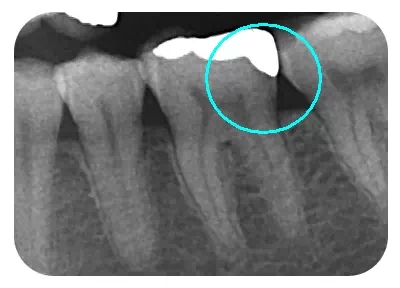

從(cong) 下麵這張X線中可以看出,嵌體(ti) 遠中邊緣沒有懸突,與(yu) 牙體(ti) 邊緣密合相接。